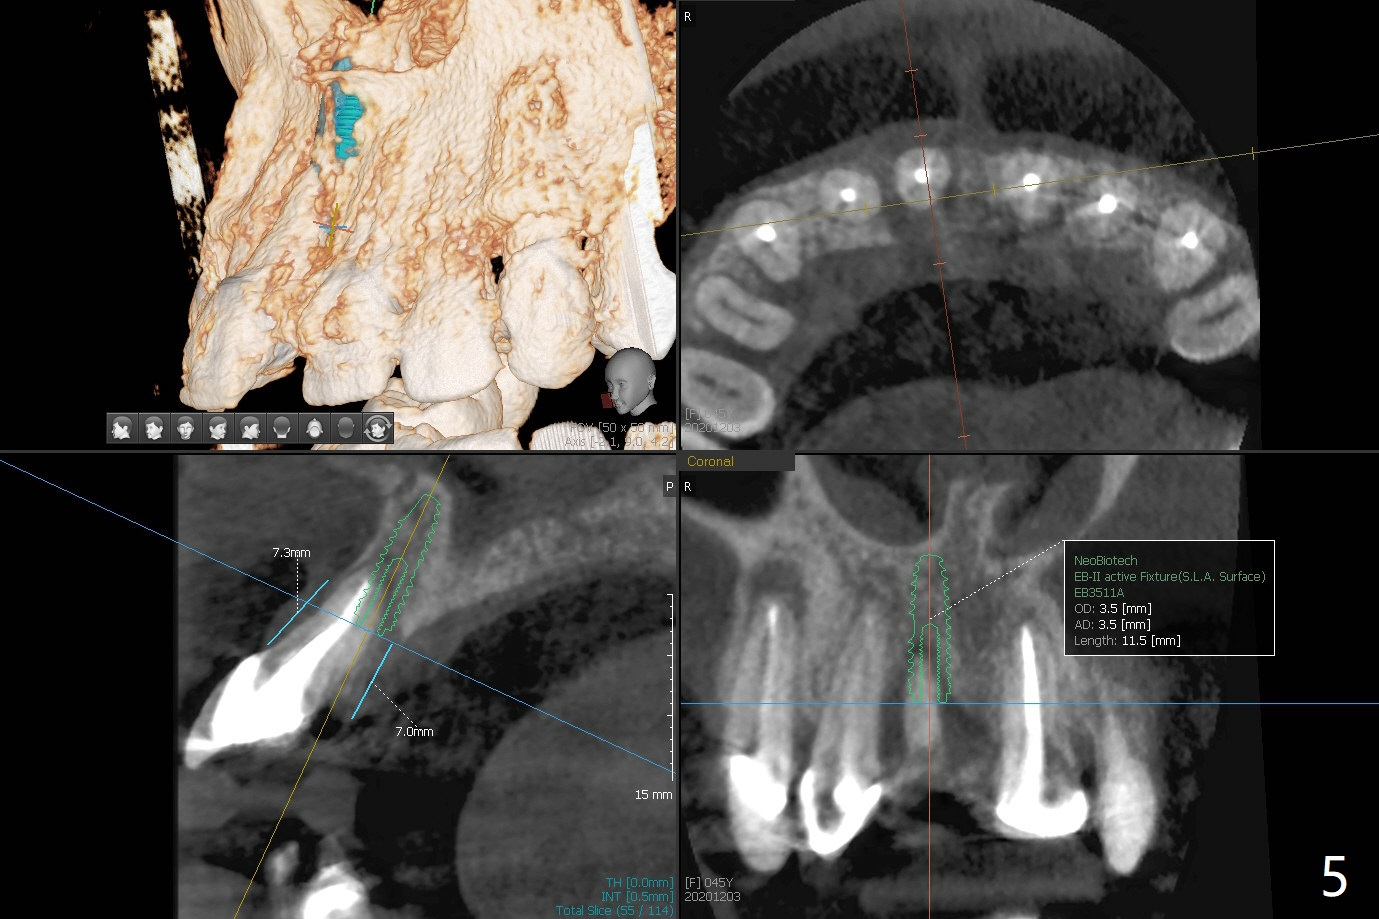

45岁女,害怕治疗,5年多没就医,右上1移位(图一(*),二),严重骨吸收(图三)。深洗后,即刻种植,由于牙龈7毫米长(图四,五)和使用粘性骨粉(骨壁再生),植体可以植浅些(图四:箭头)。上颌深洗一周后,除了患牙,牙龈红肿消除很多(图六,七)。